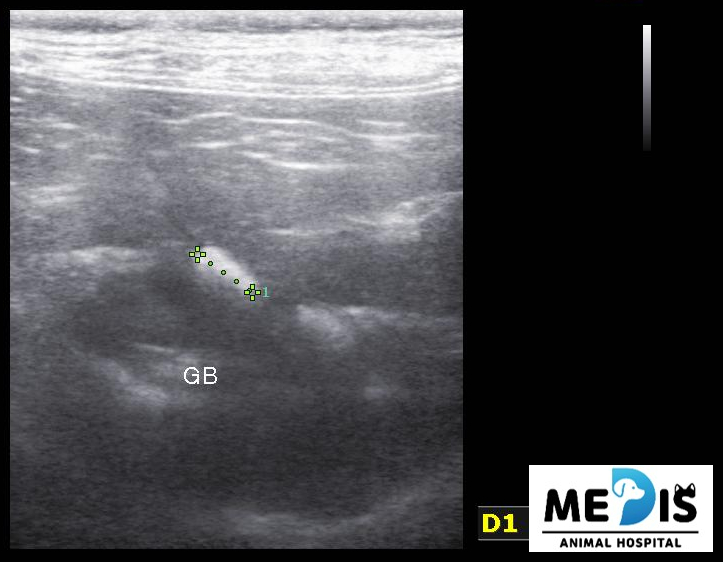

초음파에서도 담낭 주변이나 간 내부의 담도에 결석으로 의심되는 음영이 다수 관찰됐습니다.